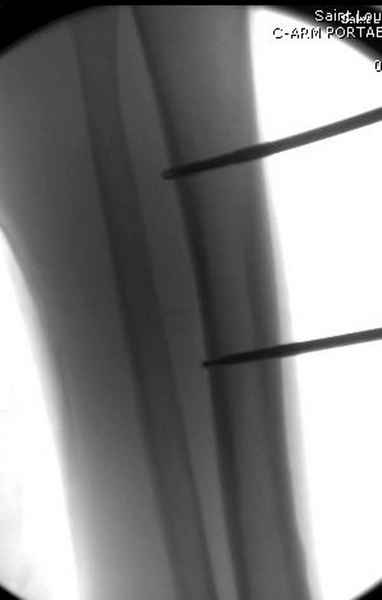

Больному с политравмой установлен наружный "spanning-bridging" фиксатор, после нескольких Irrigation&Debridment на фоне отрицательного посева из раны, через открытый участок установлен 4.5 mm Locking Plate.

На фоне фиксированного перелома бедра мероприятия по восстановлению мягкотканого покрова. Перелом голени зафиксирован после стабилизации бедра традиционным методом.

Антибиотические бусы могут быть оставлены в мягких тканях на длительный срок и не обязательно их удалять.